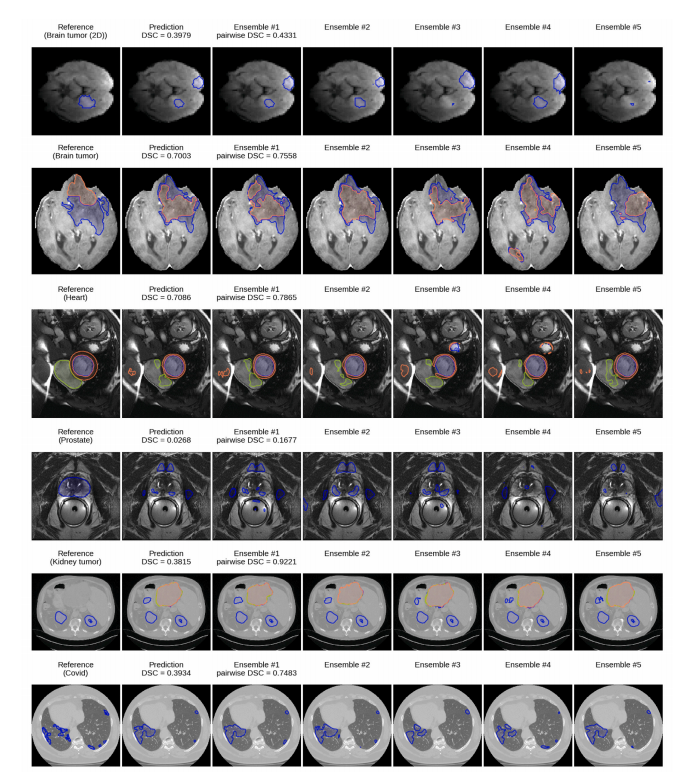

Fig. 6. Qualitative analysis of ensemble predictions on all datasets. For each dataset (rows), an interesting failure case is shown, consisting of (columns from left to right): thereference segmentation, the ensemble prediction and individual predictions of ensemble members (Ensemble #1 – 5) trained with different random seeds. True mean DSC isreported alongside the pairwise DSC scores. The ensemble predictions often disagree about test cases for which segmentation errors occur, which leads to low pairwise Dice andcan be considered a detected failure (rows 1–4). However, there are also cases where the ensemble is confident about a faulty segment, which could result in a silent failure (lasttwo rows).

图6. 对所有数据集的集成预测的定性分析。对于每个数据集(行),展示了一个有趣的失败案例,包括(从左到右的列):参考分割、集成预测和集成成员的单独预测(集成 #1 – 5),这些成员使用不同的随机种子进行训练。报告了真实的平均DSC,并附带成对DSC分数。集成预测通常对测试案例有不同的意见,特别是在发生分割错误的情况下,这导致了较低的成对Dice分数,可以视为检测到的失败(第1-4行)。然而,也有一些情况,集成对错误的分割表现出信心,这可能导致“无声失败”(最后两行)。